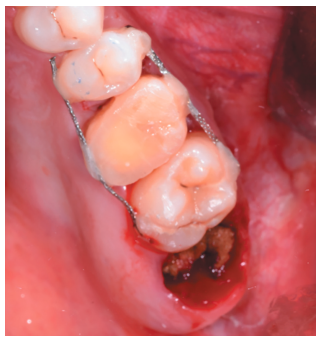

Tras rebajar la oclusión, se dio un punto en cruz con sutura monofilamento (Aragó®, Barcelona, España) alrededor del diente trasplantado para aumentar su fijación (Figura 13), realizándose una radiografía periapical intraoperatoria con técnica de paralelismo (Figura 14).